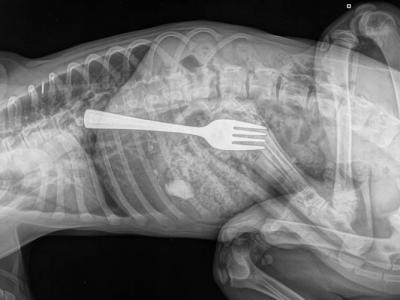

澳洲南澳省阿德莱德金毛寻回犬经常在家中

澳洲南澳省阿德莱德金毛寻回犬经常在家中偷吃食物 X光片惊见餐叉(神秘的地球uux.c...